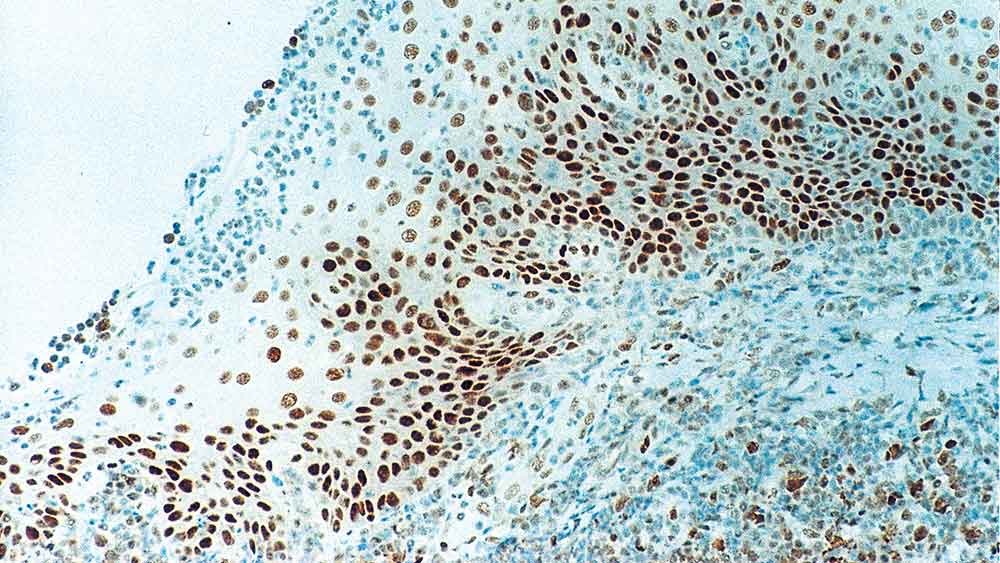

Human tonsil: immunohistochemical staining for Retinoblastoma Gene Protein. Note intense nuclear staining of epithelial cells. Retinoblastoma Gene Protein: clone 13A10

Retinoblastoma Gene Protein

Retinoblastoma (Rb) is a rare tumor of the retina associated with mutations of chromosome 13. The nuclear phosphoprotein encoded by the Rb tumor suppressor gene is present in many cells and may indirectly regulate cell growth by activating the transcription factor ATF-2. Activation of ATF-2 initiates expression of TGF-beta2, which in turn inhibits transcription of genes affecting cell growth. Bilateral mutation of the Rb gene may potentially play a role in the development of a number of malignant tumors.

NCL-L-RB-358 was raised to the N-terminal region of the Rb gene protein.